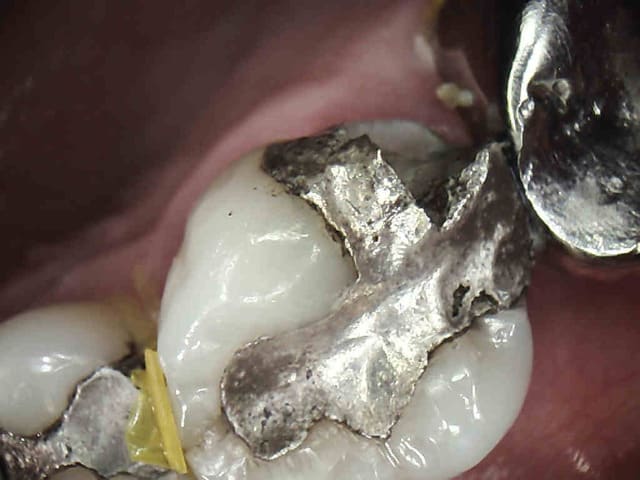

Patiente se présentant avec une fracture cuspide disto-vestibulaire de 16.

Dent ne pouvant etre reconstituée de facon durable par un matériau inséré en phase plastique ( composite, amalgame).